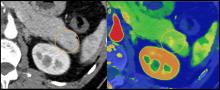

May 27, 2021 — Philips Healthcare released a workhorse computed tomography (CT) system, the Spectral CT 7500, which has regulatory clearance in Europe and from the U.S. FDA. It uses intelligent software to deliver high quality spectral images on every scan 100% of the time without the need for special protocols.